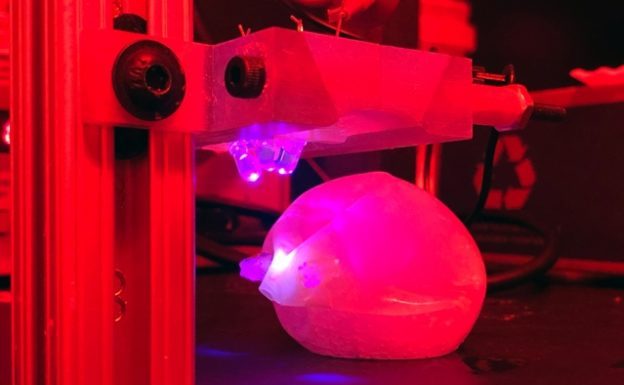

目前市面上有許多植入性治療方法,就好比食道支架、胃氣球就是一例,不過這些設備也沒有辦法在人體內久待,終究要用內視鏡或是其他設備取出,現在美國麻省理工學院研發的新醫療設備或許能省下這一環節,只要吞下特殊封裝的藍色 LED 燈,光照一照該材料就會逐漸分解,最後人體內自行吸收。